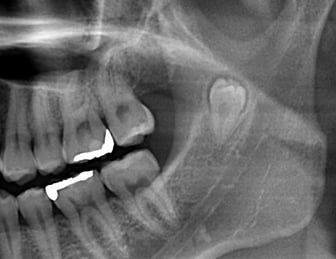

埋状歯(顎の骨または歯肉の下に埋もれて出てこない歯。)

水平埋状歯(横向きに埋もれて出てこない歯。下顎の親知らずでよく見かけます。)

過剰歯

転移歯(理想的な歯列から外れて生えている歯。矯正治療で抜歯する場合が多いです。)